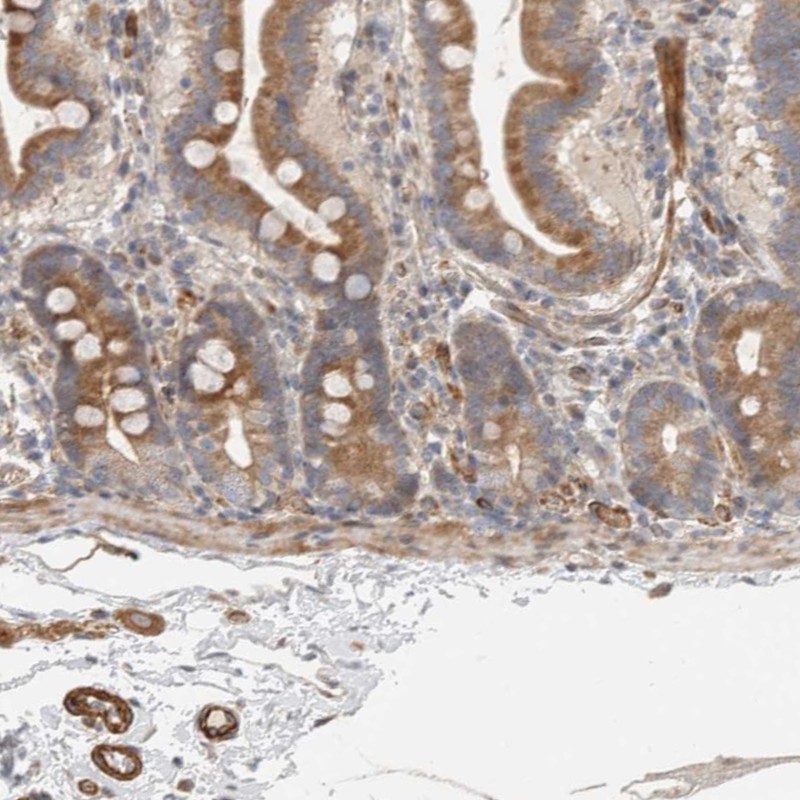

Immunohistochemical staining of human duodenum shows moderate cytoplasmic positivity in glandular cells.